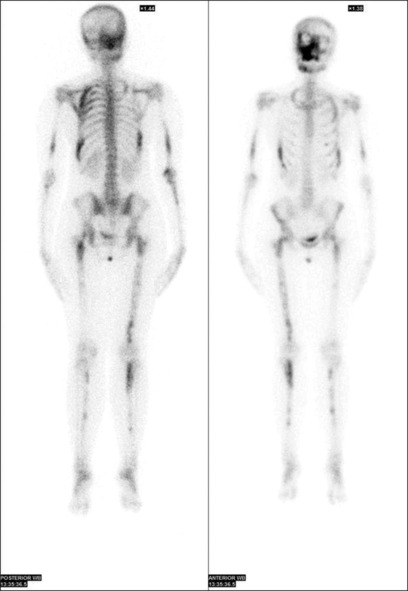

McCune-Albright syndrome is a rare and challenging disorder characterized by a triad of cutaneous, bone and multiple endocrine abnormalities. We present the case of a 15-year-old female with varied symptoms including precocious puberty, prolactinoma, polyostotic fibrous dysplasia, and hyperthyroidism. On examination, she had a palpable nodule in the right lobe of the thyroid with an atrophic left lobe on ultrasonography. Thyroid scan in this patient posed a diagnostic challenge which was resolved with additional single-photon emission computed tomography/computed tomography (SPECT/CT). On SPECT/CT, she was diagnosed with autonomously functioning thyroid nodule and treated with 15 mCi of 131I.